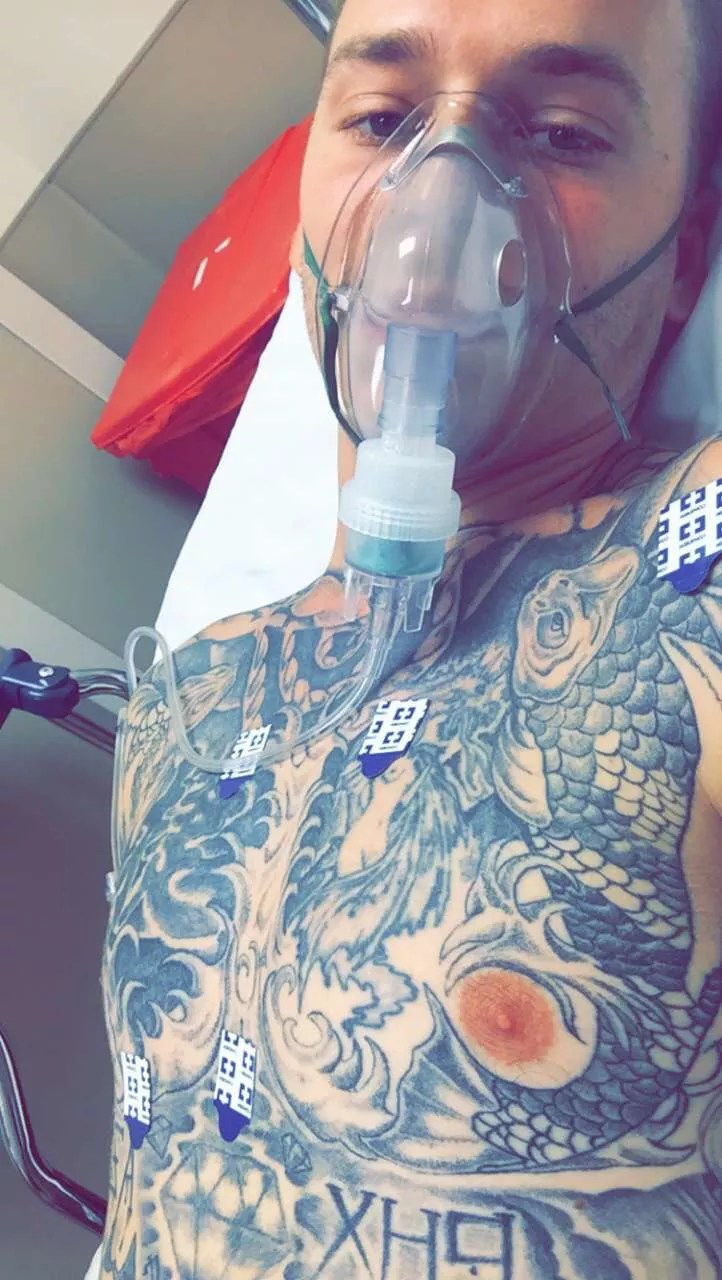

The 27-year-old man soon found himself in the hospital for four days last week hooked up to an oxygen tank, and he thinks vaping is to blame.

After his violent vomiting incident on September 4, he was taken to Abrazo Scottsdale Campus hospital and immediately put on oxygen therapy, which wasn’t stopped until he left on Saturday. After undergoing testing that included MRI and CT scans, he was diagnosed with a type of pneumonia caused by chemicals.

Before he left the hospital on Saturday, he was removed from his oxygen tank and tasked with walking a couple of laps without it. Doctors are not sure whether the damage to Levendoski’s lungs will heal completely, but he is thankful to be home. Neither Mathew nor officials with Abrazo Health returned messages.